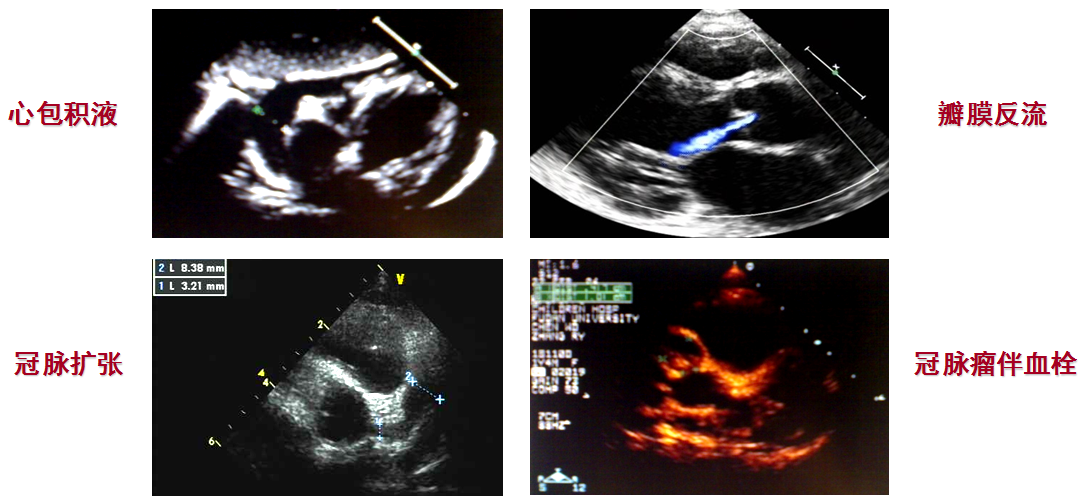

Echocardiography,ECHO (超声心动图)

▪ 病程第1~6周,可出现心包炎(pericarditis)、心肌

(myocarditis)、心内膜炎(endocarditis)、心律失常(arrhythmia)

▪ 冠状动脉损害多发生于病程第2~4周,也可发生于恢复期

冠状动脉损害:冠状动脉扩张(coronary artery dilation)

冠状动脉瘤(coronary artery aneurysms)

冠状动脉狭窄(coronary artery stenosis)

▪ 心肌梗死和冠状动脉瘤破裂可致心源性休克、甚至猝死